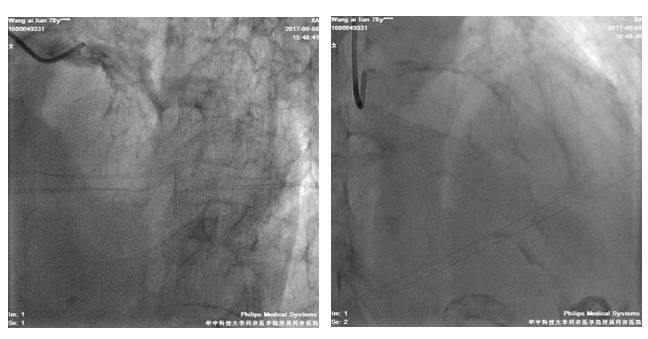

我院冠脉造影

LM严重钙化,体部散在斑块;LAD近段-中段弥漫性钙化伴狭窄,最重处约70%

LCX弥漫性钙化伴狭窄,最重处狭窄约90%

RCA开口处严重钙化,近中段弥漫性狭窄,中段最重狭窄达90%,狭窄最重处达90%,伴溃疡